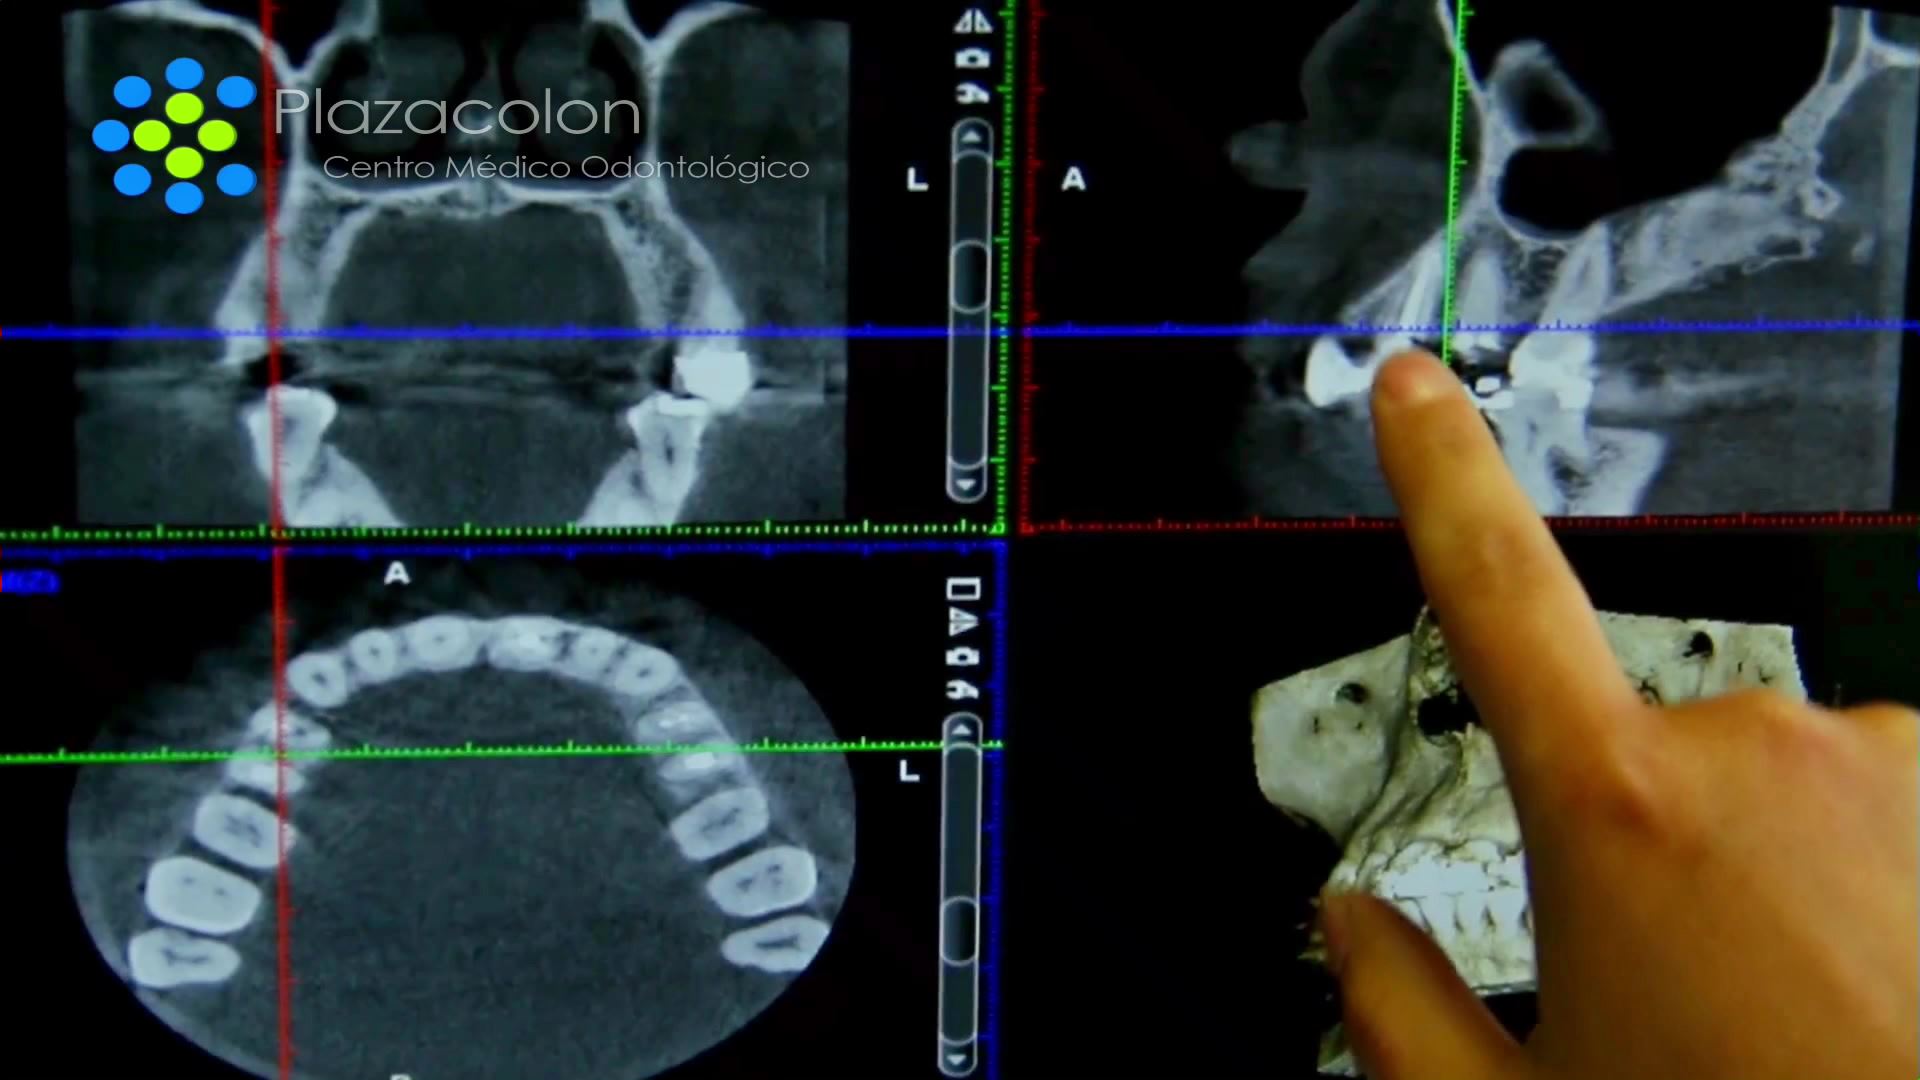

Avanzadas Técnicas

Estamos a la vanguardia en técnicas quirúrgicas implantológicas.

Planificamos tu cirugía minuciosamente para obtener el mejor resultado.